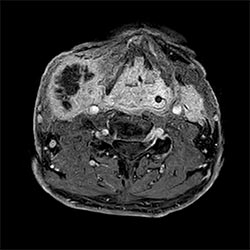

'Compressed SENSE, hızlı çekim tekniği ile görüntü kalitesinde hiçbir değişiklik yapmadan inceleme verimliliğini yükseltiyor.''

Sachi Fukushima, RT, Kurashiki Central Hastanesi, Japonya